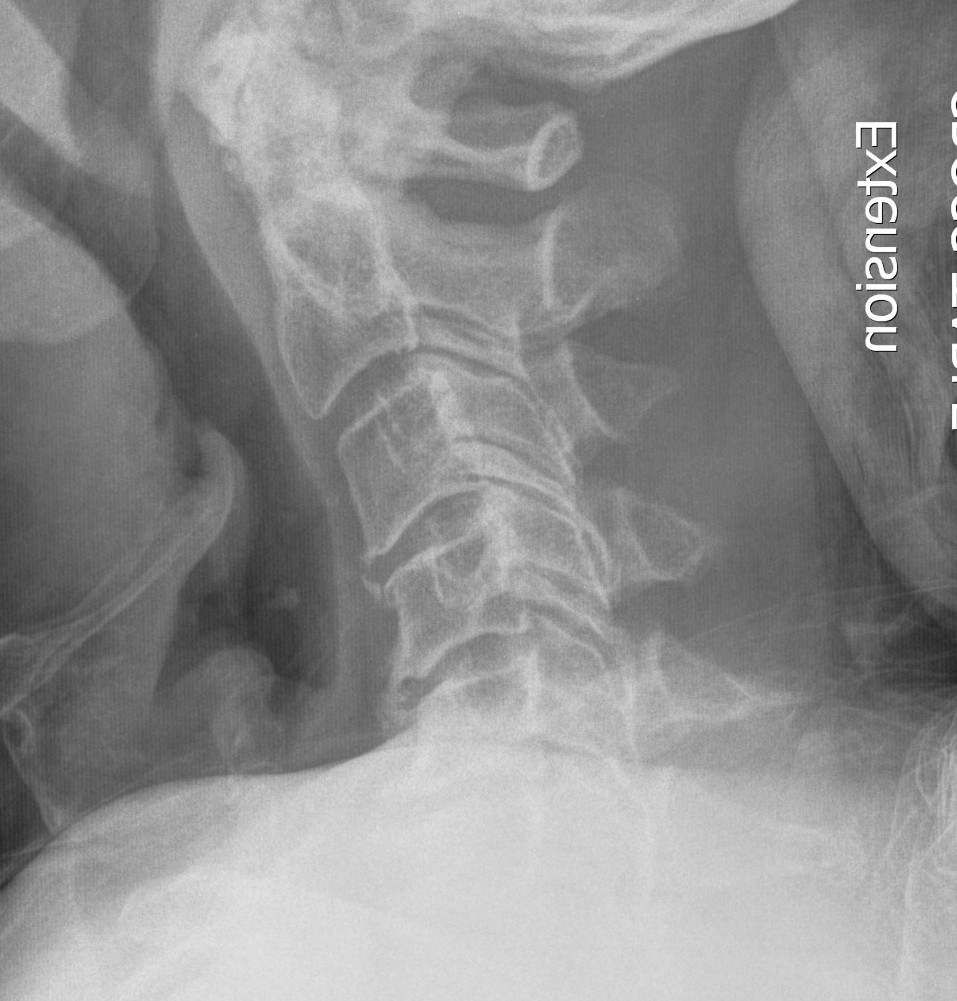

X-ray

Degenerative changes - C5/6 commonest level followed by C6/7

Alignment - lordosis v kyphosis

Ossification PLL

Flexion / Extension views show instability

- > 3 o

- > 11 mm

Torg-Pavlov's Ratio (A/B)

AP diameter of spinal canal (A) divided by the AP diameter of body (B) at same level

- should be 1.0

- < 0.8 is narrowed and stenotic